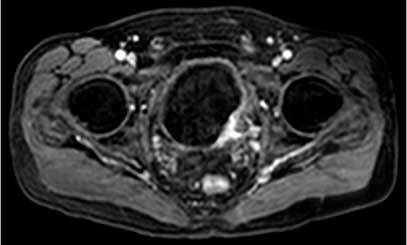

Hình 1. Hình ảnh MRI xung T1 cho thấy khối u bàng quang bên trái có tín hiệu trung gian so với tín hiệu thấp của nước tiểu trong bàng quang. Có lớp mỡ liền kề với khối u, phù hợp với giai đoạn bệnh T3b sớm.

Các chuỗi xung T1 rất hữu ích để xác định khối u nguyên phát, vì nó có thể được nhìn thấy dựa trên nước tiểu sẫm màu trong bàng quang (Hình 1). Câc chuỗi xung T1 có giá trị để đánh giá thâm nhiễm mỡ quanh bàng quang vì mỡ lân cận bàng quang có tín hiệu cao. Câc chuỗi xung T1 cũng hữu ích để đánh giá hạch hoặc di căn xương.